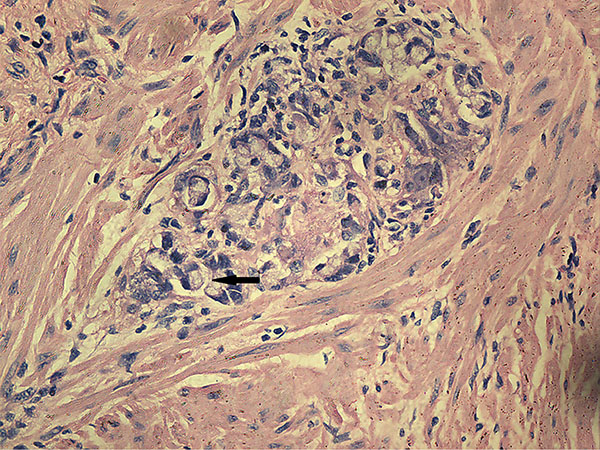

Histopathologic assessment of the primary tumor

Univariate analysis showed no differences in the tumor regression grade, incidence of T downstaging, neural invasion, or mesenteric tumor nodules (P > 0.05) between the ypN+ and ypN‒ groups. The ypN+ patients had significantly less differentiated tumors (P = 0.001), higher ypT stage (P = 0.013), and a higher incidence of lymphovascular invasion (9.8% vs. 1.2%, P = 0.038) than ypN‒ patients (Figures 2–3). In addition, mucinous or signet ring cell adenocarcinomas (poorly differentiated histological subtypes) were more commonly observed in ypN+ patients than in ypN- patients (P < 0.001) (Table 2, Figures 4–5).

Figure 5: Characteristic histological features of signet ring cell adenocarcinoma (H.E. staining, 200× magnification). The arrow indicates a signet ring cell adenocarcinoma.